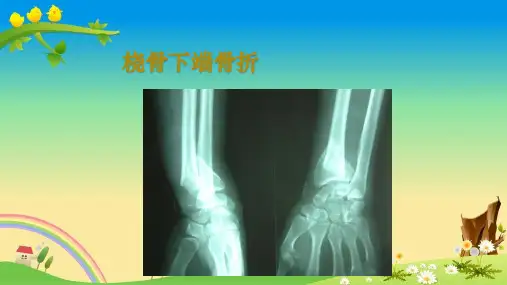

概述

多为间接暴力引起 最常见的损伤机制是跌倒时手过伸支撑 其次是运动相关损伤和交通事故 骨质疏松是老年人桡骨远端骨折多发的重要因素

桡骨远端骨折是骨科医生最常遇到的骨折之一,约占全身